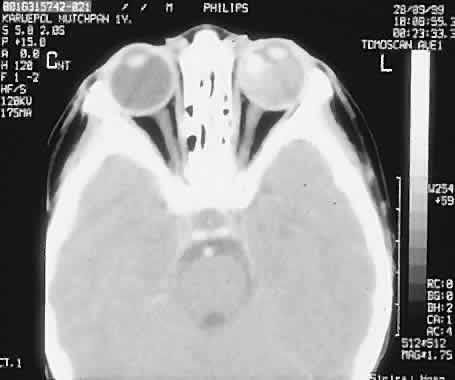

Two features of retinoblastoma are almost pathognomonic: calcification and seeding of tumor cells into the vitreous. CT can be used to confirm the presence of calcification or the extension of tumor (Fig. 6). We assess all patients for the presence of any pineal lesions associated with trilateral retinoblastoma. MRI has been shown to have remarkable sensitivity in distinguishing differences in tissue density. Its advantages are that it uses no external radiation and is a relatively noninvasive technique. With the use of a surface coil, spatial relations in the eye can be even more clearly delineated.

Fig. 6. Axial CT scan with contrast demonstrating calcification in a retinoblastoma of the left globe.